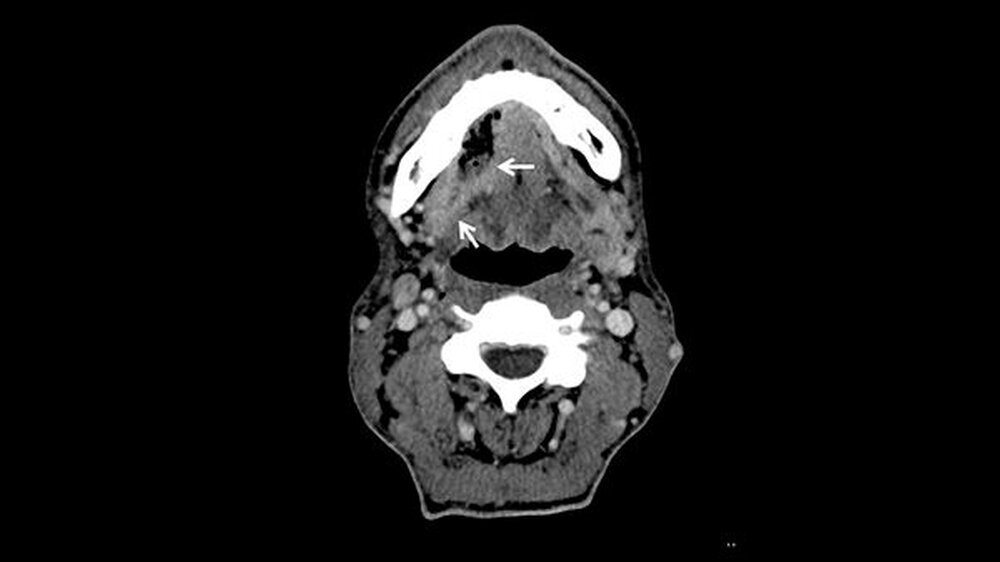

Ein Jahr nach der Exzision des Primärtumors, der begleitenden Radiatio sowie dem mikrochirurgischenAufbau des Unterkieferdefekts stellte sich der Patient erneut vor, um einen Termin zur Entfernung des Osteosynthesematerials zu vereinbaren. Bei dieser Untersuchung bemerkten die Chirurgen eine erhebliche Raumforderung am linken Oberarm, die nach Angaben des Patienten sehr schnellem Wachstum.

Weder das Röntgenbild noch die weitere Untersuchung mit magnetresonanztomografischer Bildgebung gaben eindeutigen Aufschluss. Daraufhin wurde eine Biopsie veranlasst, die die Verdachtsdiagnose einer Metastase des oralen Plattenepithelkarzinoms histologisch bestätigte.